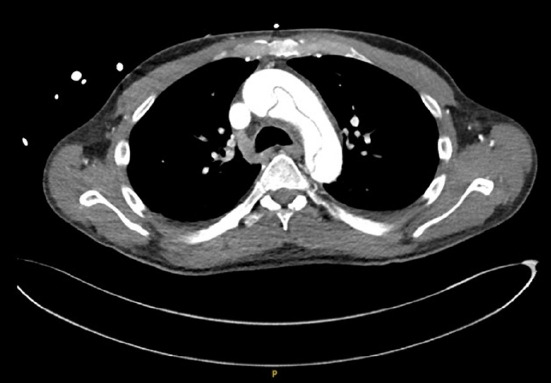

This case concerns a 59-year-old male patient with a medical history of hypertension, chronic renal insufficiency, and autoimmune pancreatitis secondary to immunoglobulin G4 (IgG4)-related disease, who was on chronic steroid treatment. The patient experienced acute onset of lightheadedness, a tingling sensation in both hands, and jaw tightness after masturbating. He was found to have type A aortic dissection. This is the first case of its kind to document an atypical, painless aortic dissection presentation in a patient with IgG4-related disease. This piece explores how the fibroinflammatory sequelae of IgG4-related disease can result in aortic manifestations and discusses the importance of considering a broader differential including aortic syndrome when encountering patients presenting with atypical symptoms.

Abstract Image